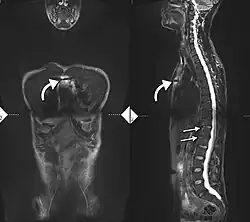

If these criteria still do not give a compelling diagnosis magnetic resonance imaging (MRI) may be useful.[22][24] MRI can show inflammation of the sacroiliac joint.

Options for earlier diagnosis are tomography and MRI of the sacroiliac joints, but the reliability of these tests is still unclear.

-

Lateral X-ray of the mid back in ankylosing spondylitis -

Lateral X-ray of the neck in ankylosing spondylitis -

X-ray showing bamboo spine in a person with ankylosing spondylitis -

CT scan showing bamboo spine in ankylosing spondylitis -

T1-weighted MRI with fat suppression after administration of gadolinium contrast showing sacroiliitis in a person with ankylosing spondylitis